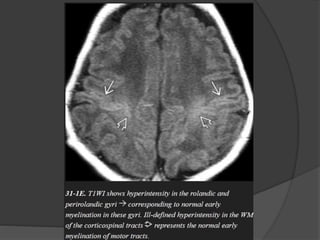

 Normal myelination… Hyperintense on T1 &

Hypointense on T2.

 Pre / postcentral gyri

 Corticospinal tract.

 Pre / post central gyri.